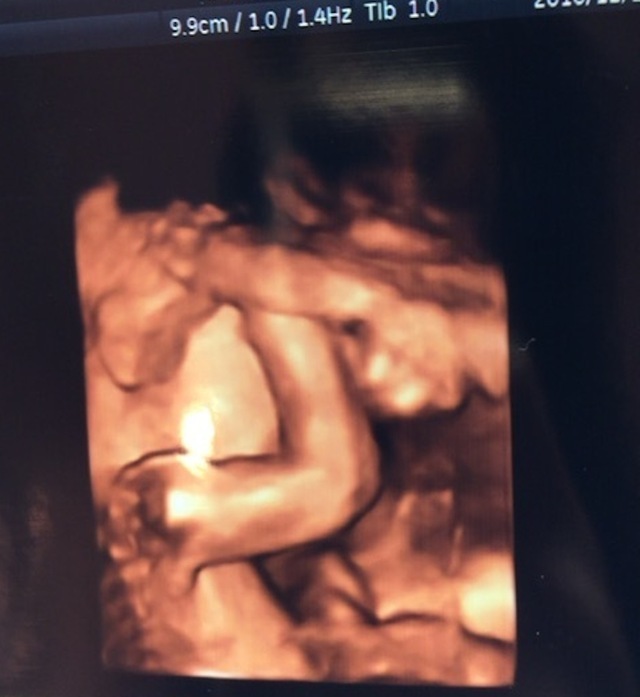

25週1日(25w1d・男の子)|plzLM_ さん(25歳)

エコー写真撮影時のエピソード:

妊娠するとトイレが近くなりますが、エコーの際はおしっこがある程度溜まっていた方が赤ちゃんがきれいに映りやすいとお医者さんが言っていたので、検診前は行かないようにしていました!

息子は常に手や足で顔を隠していましたが、それが鮮明に映っていました!